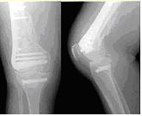

一旦罹患骨質疏鬆症,患者會駝背、脊椎或關節變形,最後行動能力會受到限制,身體無法自由的向前彎,並且一翻身就造成疼痛,而且老人家體力較差、平衡感也不好容易發生跌倒,一旦跌倒可能會造成嚴重的骨折(容易發生骨折的部位有:脊椎骨、手腕骨、股骨頸)與併發症,根據資料顯示股骨頸骨折之高齡患者,約有百分之二十於骨折後第一年併發肺炎或心臟病而死亡。